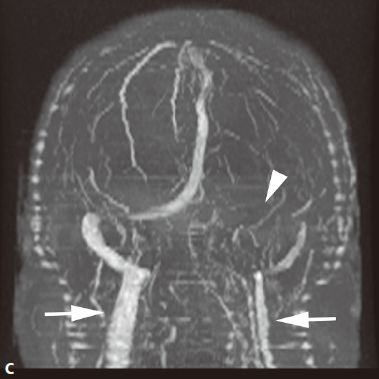

十、烟雾病

又称为脑底异常血管网症、脑底动脉环闭塞症。是以脑内虹吸段至大脑前、中动脉近端狭窄或闭塞,同时伴有广泛侧支循环形成,导致颅底出现异常毛细血管网为特征的脑血管病。好发年龄10岁以下和40-50岁。临床表现为脑缺血和脑出血两大类。儿童多为颈内动脉系统缺血性改变,成人多为颅内出血。

1. CT平扫表现为双侧额叶、顶叶及颞叶皮质或皮质下区多发脑梗死及脑萎缩改变,也可以出现颅内出血。增强有时可见到颈内动脉及大脑前中动脉粗细明显不对称,或者充盈不良,甚至不显影。可显示基底池及基底节区的侧支循环网,大多表现为为不规则的扭曲成团的强化血管影。

2. MRI表现为脑缺血引起的T1WI低、T2WI高信号脑梗死区,颈内动脉及大脑中动脉主干的“流空效应”变弱或消失,异常血管网在T2WI上表现为基底节区和鞍上池内多发细小血管影,呈网状低信号或无信号区。皮质侧支循环形成时,增强扫描可见皮质血管增多、扩张、强化、呈“常春藤征”。

3. MRA可直接显示颈内动脉、大脑前、中动脉狭窄或闭塞,于颅底见烟雾状异常血管网,常可见到颈外动脉和椎-基底动脉分支代偿性增粗。

4. 脑血管造影是确诊烟雾病的主要检查方法,可显示狭窄或闭塞的动脉及异常扩张的血管网。